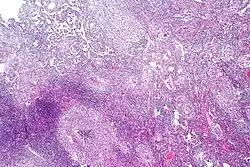

Pulmonary tuberculosis characterized by granulomatous inflammation with necrotizing epithelioid granulomas. Low power view. H&E stain. -

Pulmonary tuberculosis featuring necrotizing granulomas, H&E stain. -

Pulmonary tuberculosis featuring necrotizing granulomas, high power view, H&E stain. -